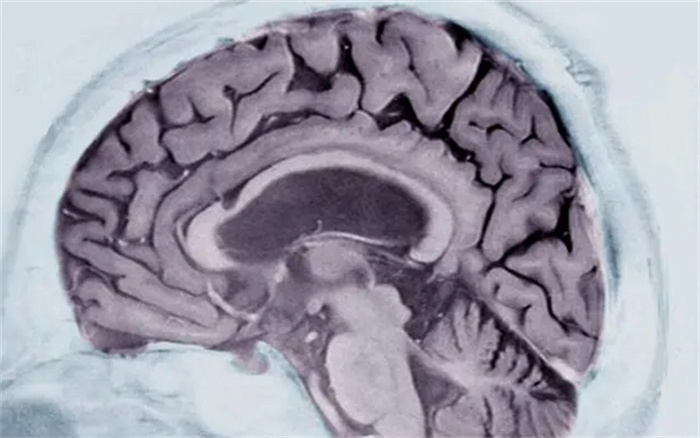

科学家发明了一套机器学习系统,用这套系统只需分析问诊者的一次脑部核磁共振(MRI)扫描的数据,即可判断其是否患有阿兹海默症。研究者称准确率高达98%。

6月20日发表于《自然》(Nature)旗下的《医学通讯》(Communications Medicine)期刊上的一份研究介绍了一种新的方法,只需问诊者接受一次脑部核磁共振扫描即可完成诊断。

研究称他们借鉴了一套对癌肿瘤分类的算法,修改后用于分析脑部扫描数据。他们把大脑分成115个区域,分别检查这些区域的体积、形态、质地等一共660项特征进行评估,并训练这套机器学习算法找到检查对象脑组织与正常脑组织的差异,从而诊断是否患有阿兹海默症。